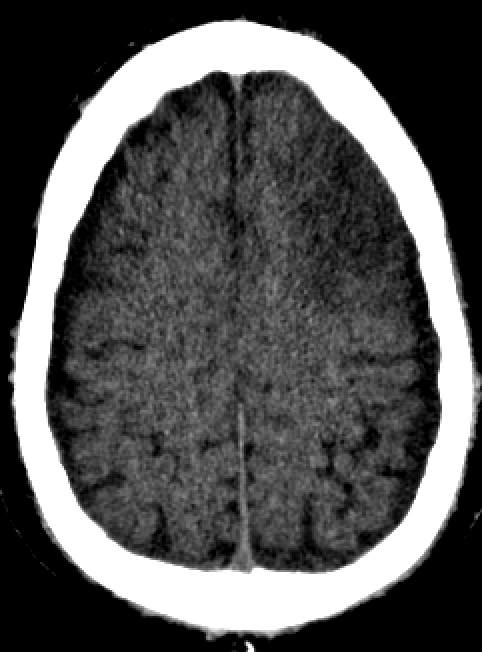

(🧵3/3) Fortunately this was a dual energy CT. The virtual non-contrast images eliminate doubt. This is contrast staining of an infarct and subdural hygromas. Anticoagulation can be continued. Contrast staining could have been inferred without DECT. But confirmation is nice!